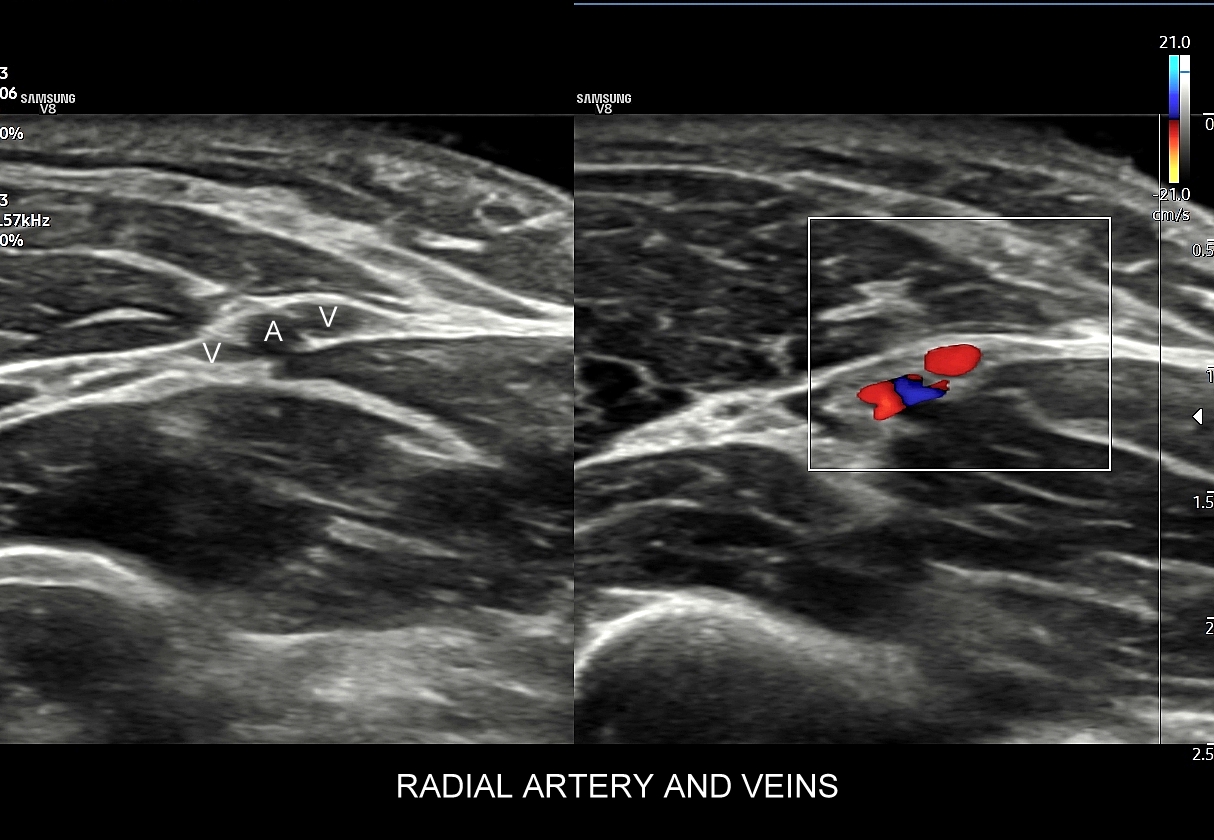

- Z kolei profile o wysokiej pulsacyjności charakteryzują się tym, iż posiadają wąskie i ostre piki skurczowe, a w fazie rozkurczowej odwrócone lub/i nieobecne przepływy. Profile tego typu występują w tętnicach unaczyniających kończyny.

Podsumowując, przepływ krwi w konkretnych tętnicach, w tym jego przyspieszenie i prędkość, wynikają z 1/ charakteru pracy pompy, tj. serca; 2/ stanu naczyń per se, tj. elastyczności i drożności; oraz z 3/ właściwości biologicznych unaczynionego narządu. W związku z powyższym prawidłowy profil przepływu we wszystkich rodzajach tętnic w krążeniu dużym w warunkach fizjologicznych, tj. przy zdrowym sercu, zdrowych naczyniach i zdrowym docelowym narządzie, zawsze cechuje się szybkim narastaniem prędkości przepływu, czyli stromym ramieniem wstępującym; krótkim czasem akceleracji (ang. acceleration time) od początku tegoż ramienia do pierwszego załamania na nim, tj. zasadniczo nie przekracza 70 ms, a zwykle oscyluje wokół 30 ms. Poza tym w przypadku młodych i elastycznych tętnic podążających do kończyn, tj. naczyń z przepływem wysokooporowym, w fazie rozkurczowej przepływu obserwuje się wyższe załamki i często więcej załamków (zamiast jednego nawet do trzech). W krążeniu płucnym czas akceleracji prawidłowo przekracza 100 ms.

W przypadku tętnic podążających do kończyn w warunkach spoczynkowych obserwuje się charakterystyczne wielozałamkowe profile przepływów zawierające od 2 do nawet 4 następujących po sobie przeciwstawnych załamków o zmniejszającej się amplitudzie, przy czym w tętnicach tych zwykle nie obserwuje się ciągłego przepływu w fazie rozkurczowej. Stały lub prawie stały przepływ rozkurczowy, tj. przepływ o pośredniej pulsacyjności, może pojawić się w tętnicach kończyn w trakcie intensywnego wysiłku fizycznego.